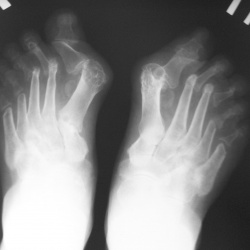

Женщина, 1968г., пришла на рентген стоп, поциентка кожной клиинки.